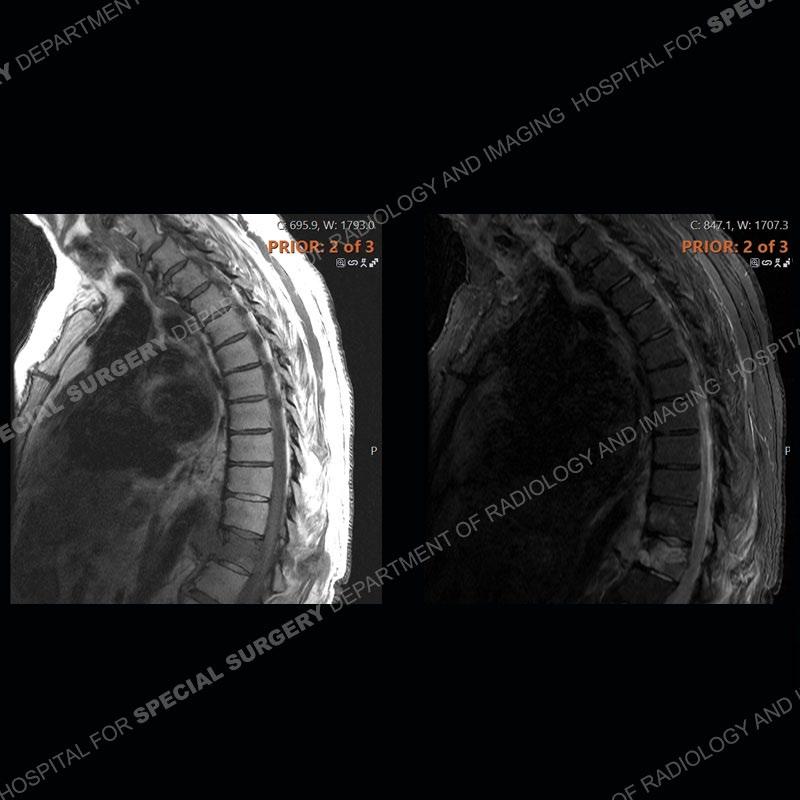

The initial MRI shows edema with a subtle fracture of the T11 vertebral body extending into the posterior elements. The subsequent MRI demonstrates a persistence and increased edema of the T11 body and posterior elements, anterior paraspinal edema/hematoma, and a progressive loss of the architecture of the T11 vertebrae. Seen well on the axial images of the MRI is the loss of CSF of the thecal sac/severe stenosis and severe right neural foraminal stenosis. The CT examination shows the loss of architecture of T11 from continued fracture and collapse. Well seen also is paravertebral osteophyte formation with bony bridging and bony bridging of the facet joints. There is an overall relative preservation of the disc spaces.

Diagnosis: DISH fragility fracture